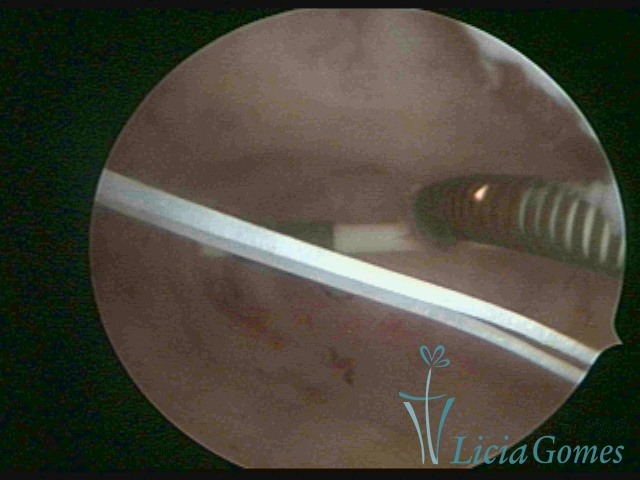

Canal cervical com fio do DIU